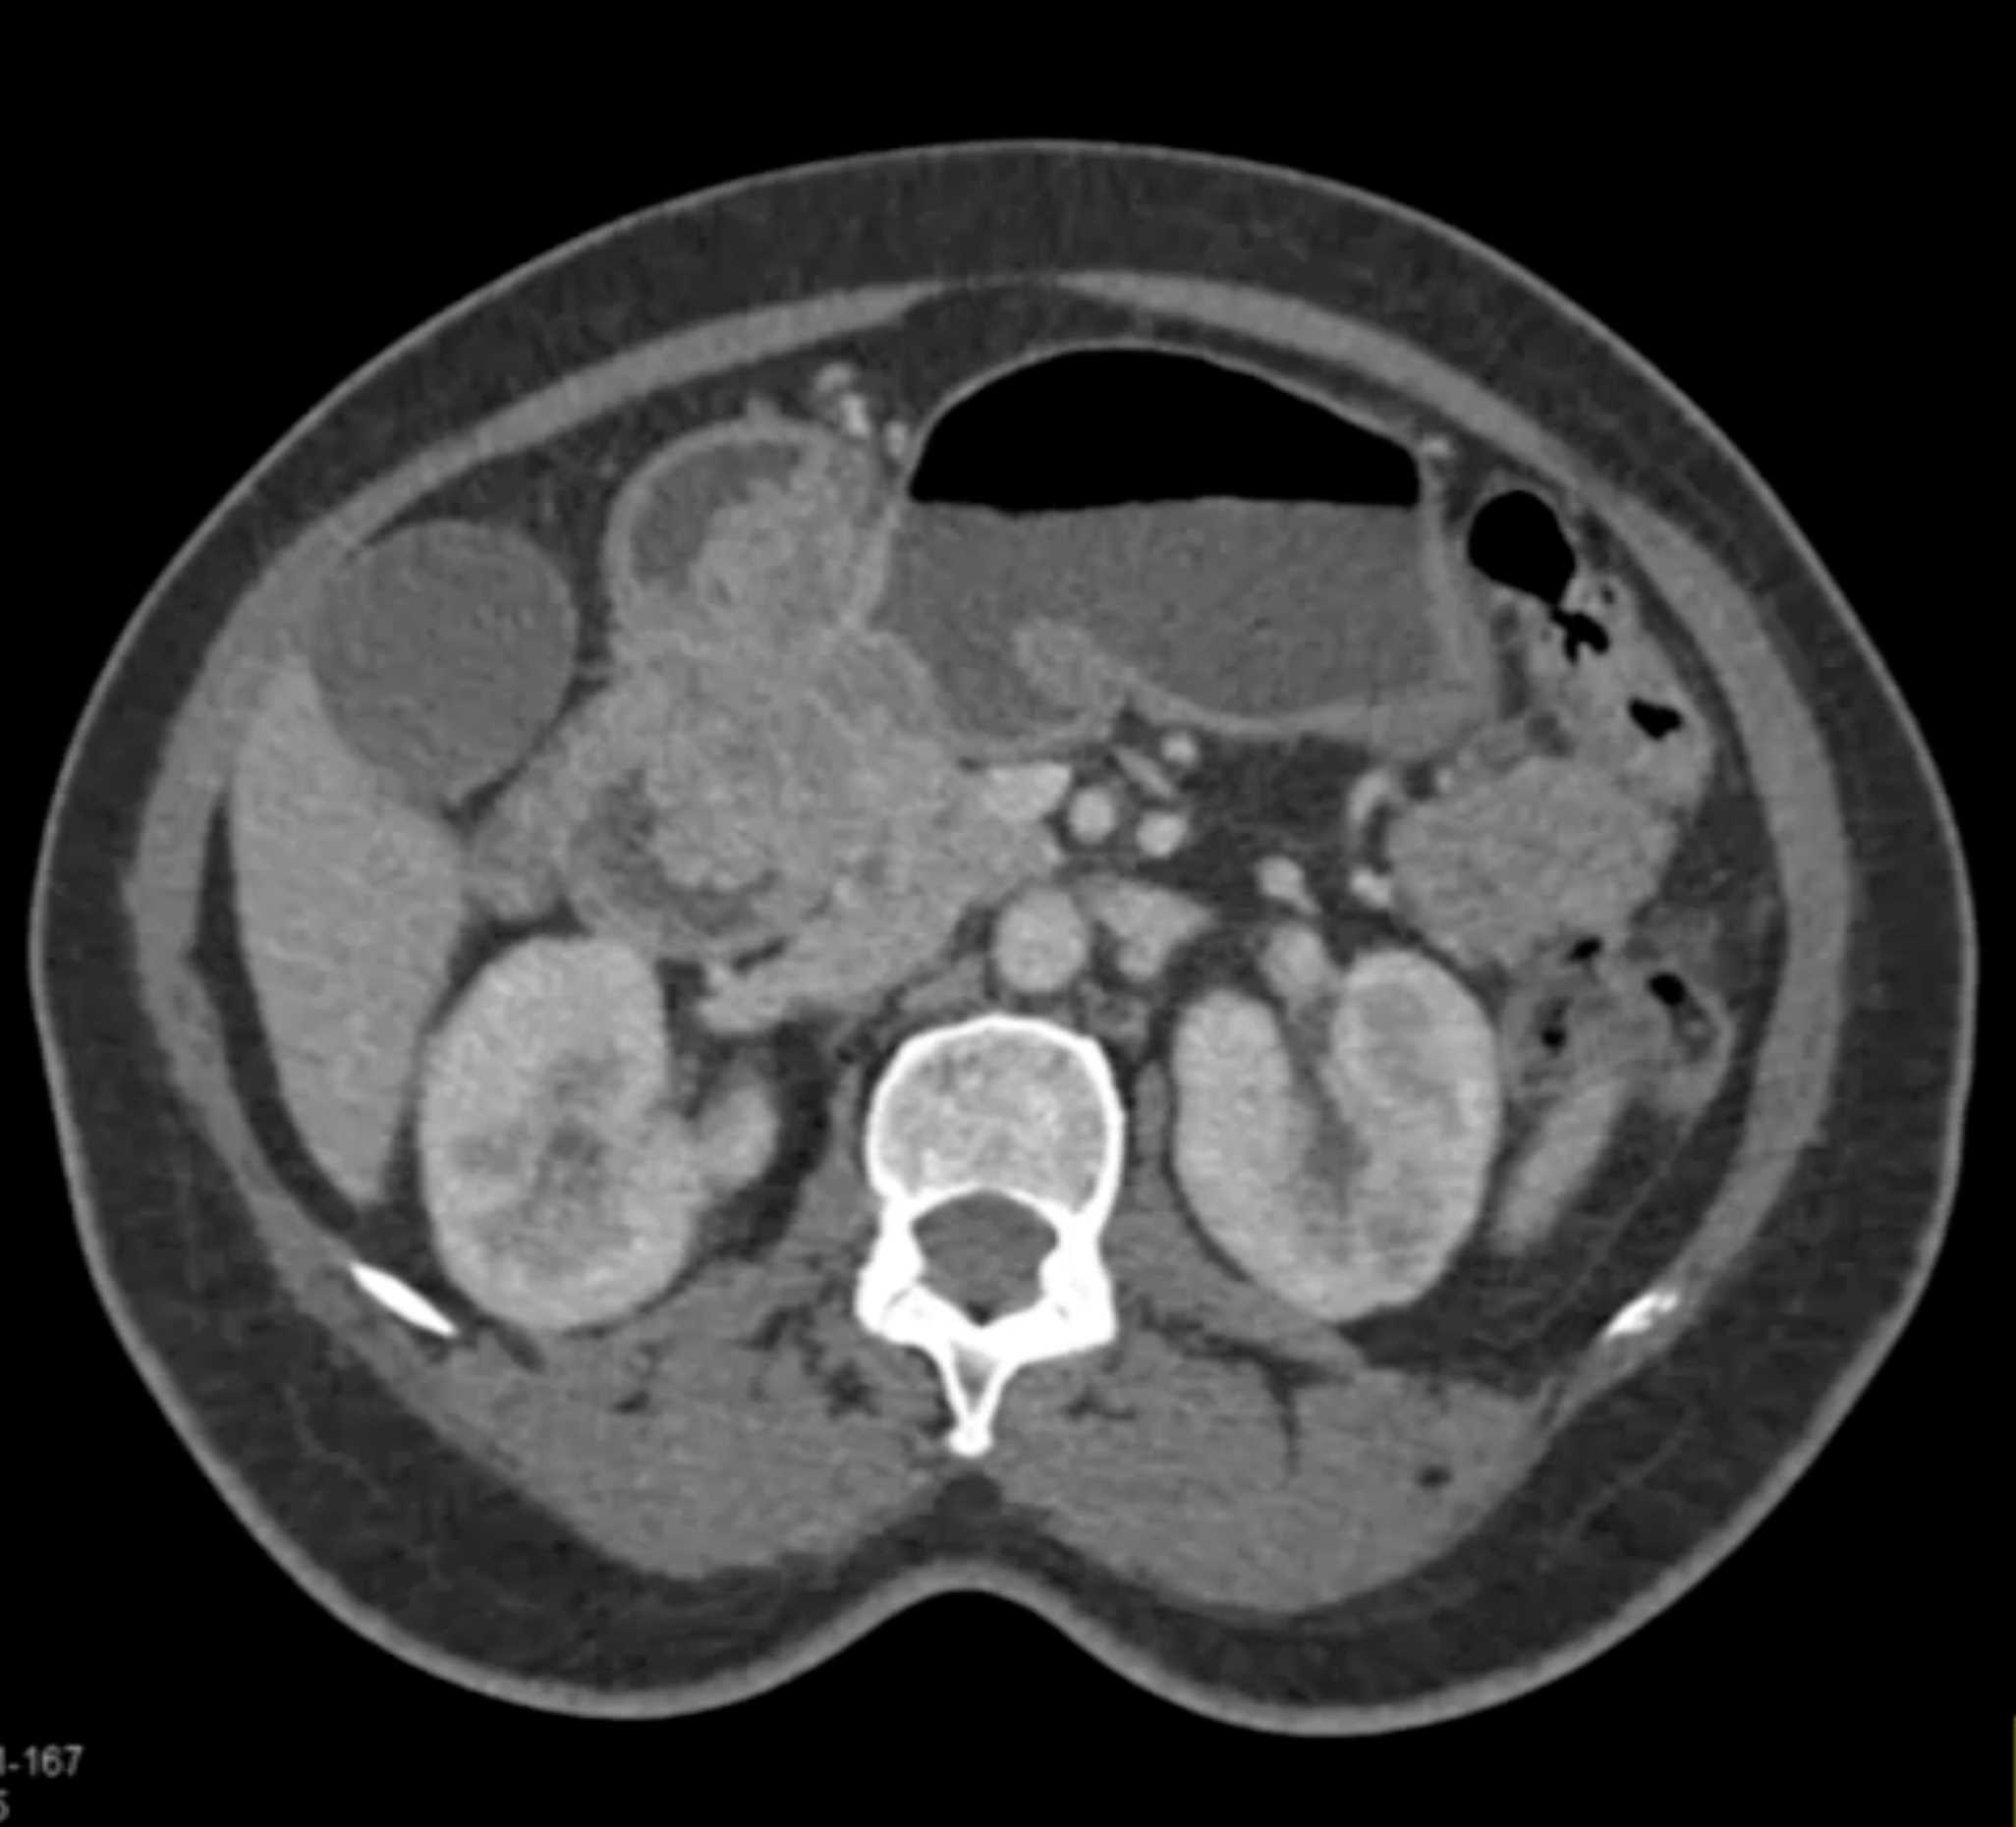

Lagre Gastric GIST Tumor